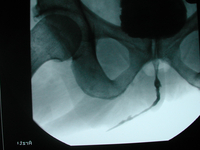

Vor der operativen Versorgung von Zysten oder Divertikeln der weiblichen Harnröhre (sog. paraurethrale Zysten oder Divertikel) sind die diagnostischen Massnahmen zur optimalen Operationsplanung von größter Bedeutung. Daher wurde in der Urologischen Klinik u. a. neben einem High-End Ultraschallgerät zur Harnröhren- und Introitus-Sonographie ein Multi-Channel Urodynamik Arbeitsplatz beschafft. Darüber hinaus wurde im Klinikum eine spezielles Programm zur optimalen Darstellung der Harnröhre und deren Erkrankung für die Kernspinuntersuchung (MRT) der Harnröhre etabliert. Wegen der Seltenheit von Harnröhrendivertikeln und paraurethralen Zysten und der hohen Gefahr der Harninkontinenz und Fistelbildung als schlimmste Komplikationen der Operation, sollten Eingriffe bei weiblichen Harnröhrenerkrankungen nur in speziellen urologischen Zentren -wie der urologischen Klinik im Klinikum Ingostadt – mit umfangreicher Erfahrung auf diesem Gebiet vorgenommen werden.